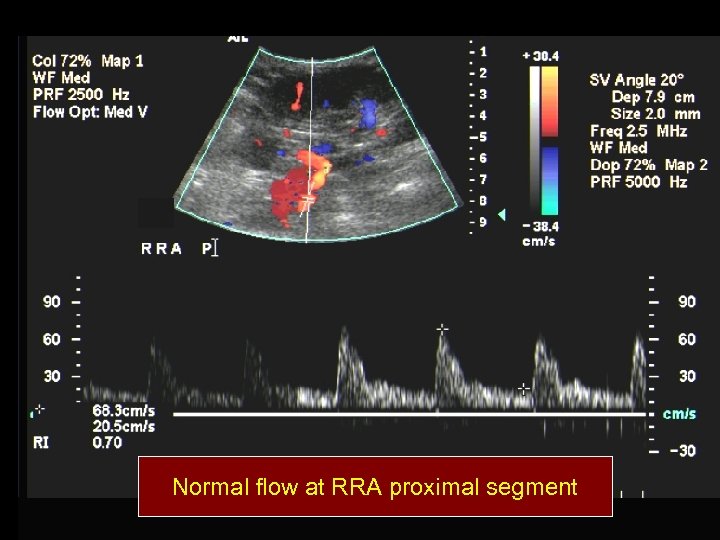

Normal flow at RRA proximal segment